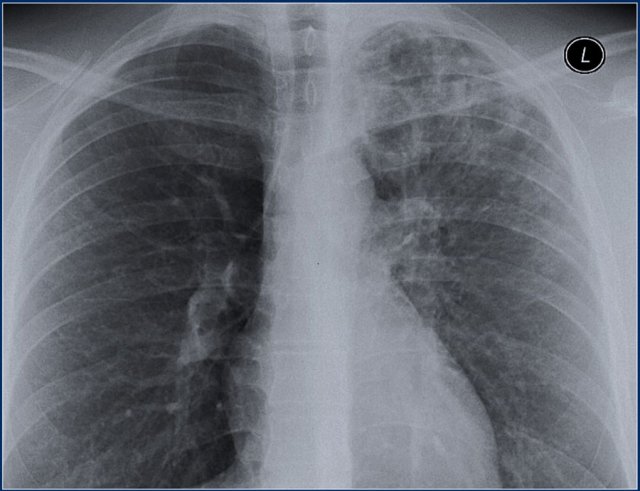

A 70-year-old male smoker presents with cough and sputum production, but is afebrile. Lung examination reveals left-sided crackles, rhonchi, and egophony in the left upper lobe. The patient is being treated for an acute exacerbation of chronic bronchitis, and sputum is negative for AFB. What is the most likely cause of the observed chest X-ray findings in the left upper lobe?

Explanation: ***Old granulomatous disease*** - **Healed tuberculosis** commonly causes **fibrotic scarring** and **calcifications** in the left upper lobe, which appear as persistent radiographic changes on chest X-ray. - The **AFB-negative sputum** and **afebrile** presentation rule out active TB, while the **upper lobe predilection** and **chronic radiographic changes** are characteristic of old granulomatous disease. *Chronic bronchitis* - Typically causes **hyperinflation** and **increased bronchovascular markings** throughout both lungs, not localized upper lobe changes. - Does not produce the **consolidation** or **fibrotic changes** that would cause **egophony** and localized crackles in one specific lobe. *Left upper lobe pneumonia* - Would present with **fever**, **acute onset** of symptoms, and **leukocytosis**, which are absent in this afebrile patient. - **Pneumonia** typically shows **acute consolidation** rather than the **chronic fibrotic changes** suggested by the clinical context and imaging findings. *Asbestos exposure* - Primarily causes **bilateral lower lobe fibrosis** and **pleural plaques**, not upper lobe predominant changes. - Associated with **restrictive lung disease** and **pleural effusions**, rather than the upper lobe consolidation pattern described.